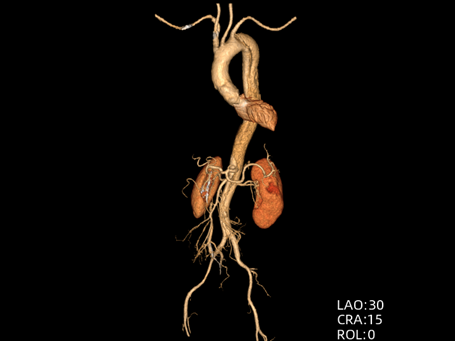

时间就是生命。医生会结合症状,快速进行以下检查:医院会根据CT血管成像(CTA)进行诊断。如确诊为主动脉夹层,则会进行紧急处理,立即镇痛、控制血压和心率(如静脉注射β受体阻滞剂)。

主动脉腔内修复术:微创治疗。通过大腿根部的股动脉,将一个覆膜支架送入主动脉夹层部位,像打补丁一样覆盖住内膜破口,使血流不再进入假腔,促进假腔血栓化愈合。

无论是术后还是药物治疗的患者,都需要终身服用降压药和降低心率的药物(如β受体阻滞剂),以降低主动脉壁的张力。必须遵医嘱定期(如术后3、6、12个月,之后每年)进行CTA或超声检查,监测主动脉全程情况,及时发现新问题。避免“高压”行为:禁止剧烈运动和重体力劳动,保持大便通畅,预防感冒引起的剧烈咳嗽。